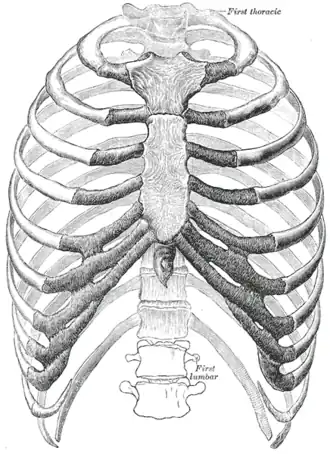

O tórax[1] é uma parte da anatomia dos mamíferos e outros animais tetrápodes localizada entre o pescoço e o abdômen.[2][3] Em insetos, crustáceos e nos extintos trilobitas, o tórax é uma das três principais divisões do corpo da criatura, cada uma das quais, por sua vez, é composta de múltiplos segmentos.

O tórax humano inclui a cavidade torácica e a parede torácica. Ele contém órgãos, incluindo o coração, os pulmões e o timo, bem como músculos e várias outras estruturas internas. Muitas doenças podem afetar o tórax, e um dos sintomas mais comuns é a dor torácica.